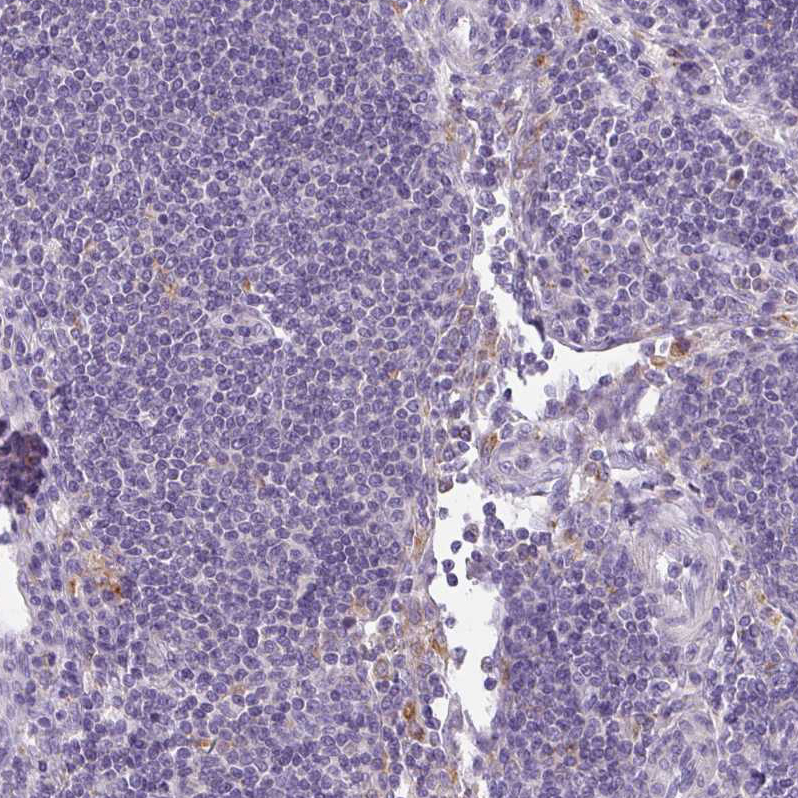

Immunohistochemical staining of human kidney, liver, lymph node and skeletal muscle using Anti-ATP6V1D antibody HPA031515 (A) shows similar protein distribution across tissues to independent antibody HPA057316 (B).